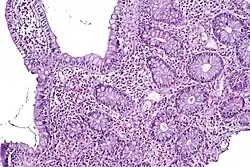

Campylobacteriosis is an infectious disease caused by bacteria of the genus Campylobacter. In most patients presenting with campylobacteriosis, symptoms develop within two to five days of exposure to the organism and illness typically lasts seven days following onset.[24] Infection with C. jejuni typically results in enteritis, or inflammation of the small intestine, which is characterized by abdominal pain, voluminous diarrhea (often bloody), fever, and malaise. Individuals infected with this bacteria can experience a prodromal phase of symptoms for the first 1 to 3 days, in which the more severe portion of the disease occurs. The prodromal phase presents with symptoms including rigors, high fever, body aches, and dizziness. Other than the prodromal phase, the acute diarrheal phase of enteritis usually lasts around 7 days, however abdominal pain can persist for weeks afterward.[3] The disease is usually self-limiting; however, it does respond to antibiotics. Severe (accompanying fevers, blood in stools) or prolonged cases may require erythromycin, azithromycin, ciprofloxacin, or norfloxacin. Fluid replacement via oral rehydration salts may be needed and intravenous fluid may be required for serious cases.[24] Possible complications of campylobacteriosis include Guillain–Barré syndrome and reactive arthritis.[3]

To initiate infection, C. jejuni must penetrate the gut enterocytes.[30] C. jejuni releases several different toxins, mainly enterotoxin and cytotoxins, which vary from strain to strain and correlate with the severity of the enteritis (inflammation of the small intestine). During infection, levels of all immunoglobulin classes rise. Of these, IgA is the most important because it can cross the gut wall. IgA immobilises organisms, causing them to aggregate and activate complement, and also gives short-term immunity against the infecting strain of organism.[31] The bacteria colonize the small and large intestines, causing inflammatory diarrhea with fever. Stools contain leukocytes and blood. The role of toxins in pathogenesis is unclear. C jejuni antigens that cross-react with one or more neural structures may be responsible for triggering the Guillain–Barré syndrome.[10]